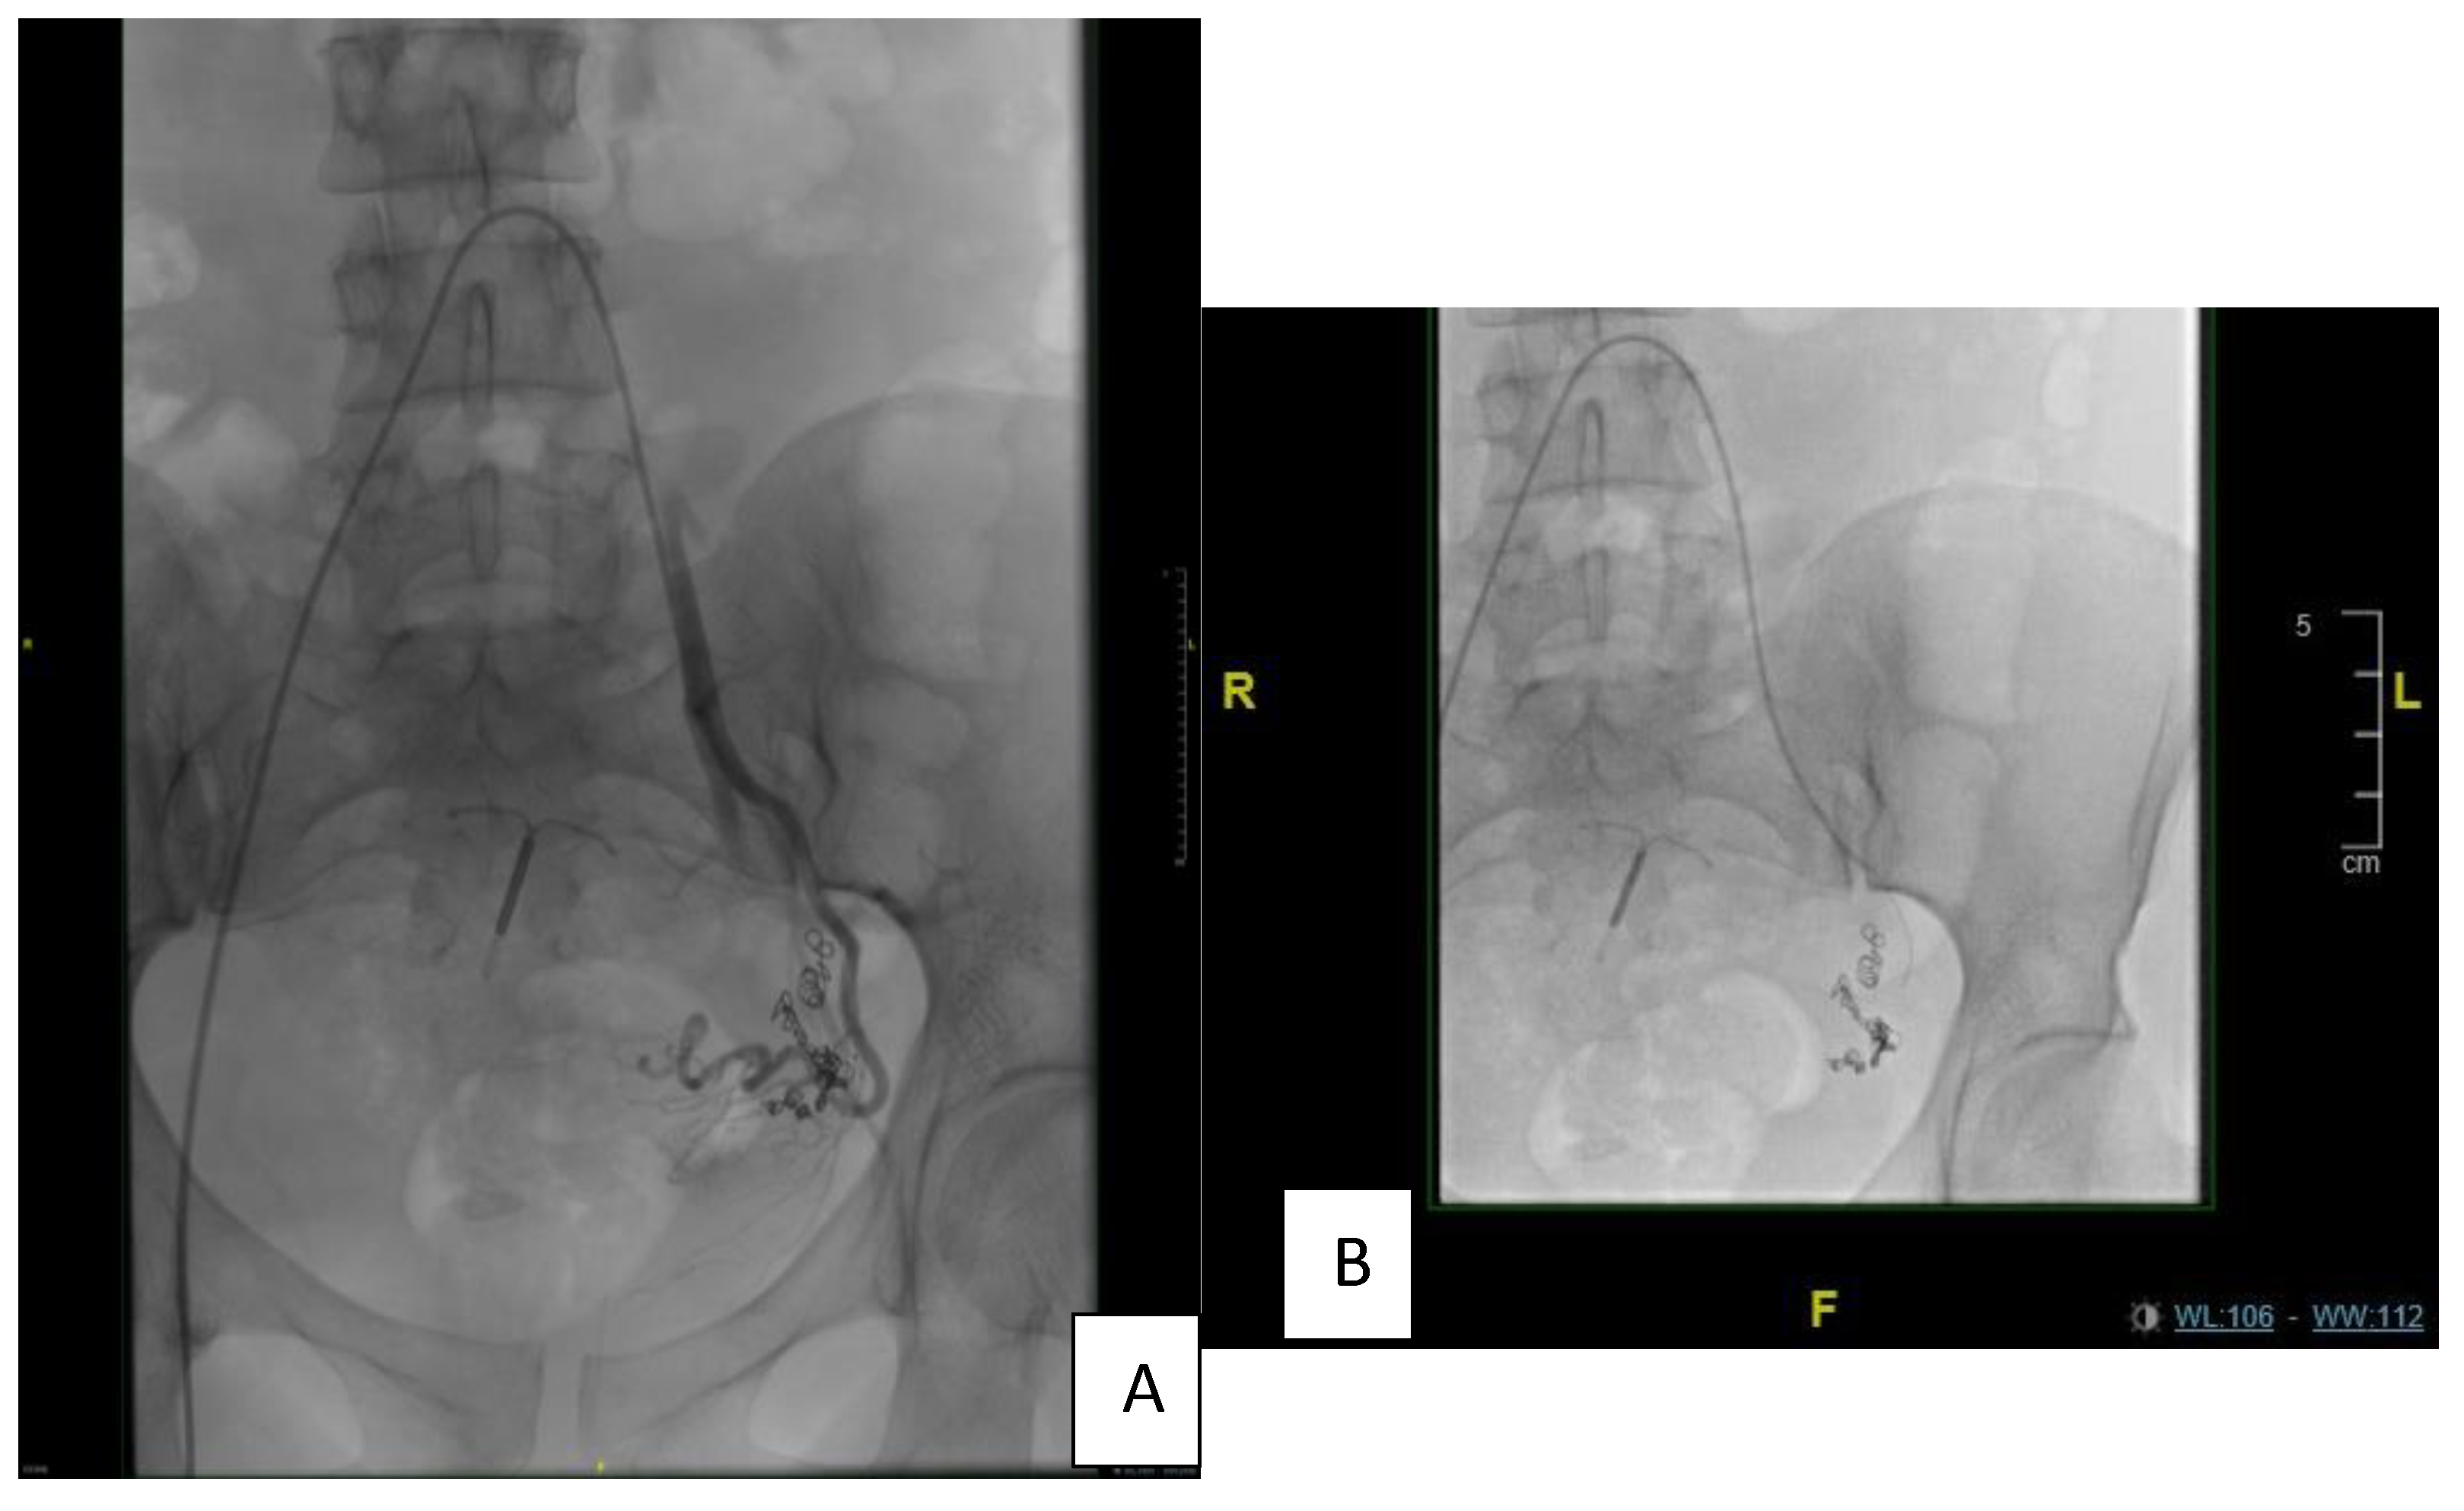

| First angioembolization | Selective catheterization of the left internal iliac artery using a C2 angiocatheter followed by angioembolization of the left superior vesical arteries, approaching from the anterior division of the left internal iliac artery. |

| In 2018, second angioembolization | The patient underwent selective catheterization of the left internal iliac artery using a C2 angiocatheter; selective angiography revealed recanalization of the previously embolized left superior vesical arteries from the anterior division of the left internal iliac artery and supplying the known intra-resulting AVM. Selective catheterization of the left superior vesical artery using a 3F microcatheter, followed by embolization of the artery, was executed using ONYX. |